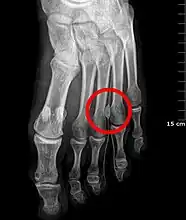

The plantar nerves, with the most common involved location circled.

Morton's neuroma is a thickening of the nerve, usually between the third and fourth toe.[3] The main symptoms are forefoot pain, numbness, and burning.[1] The pain may be shooting or stabbing and worsened with walking.[3][5] Some may describe a pebble sensation.[5] It may worsen over time.[5]